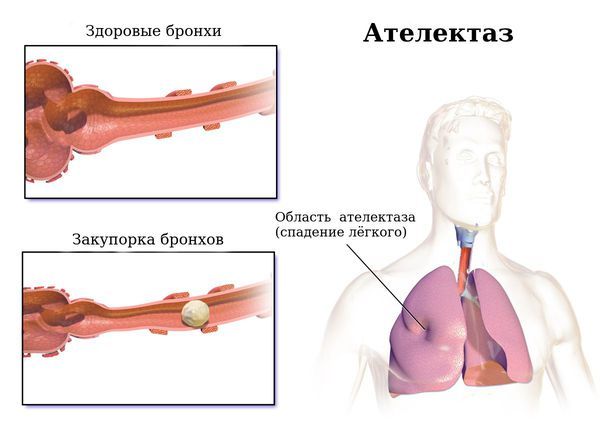

9. Ателектаз — спадение доли, сегмента или субсегмента лёгкого за счёт сужения просвета соответствующего бронха и развития клапанного механизма, когда воздух проходит по бронху при выдохе, но не поступает обратно при вдохе.

Ателектаз